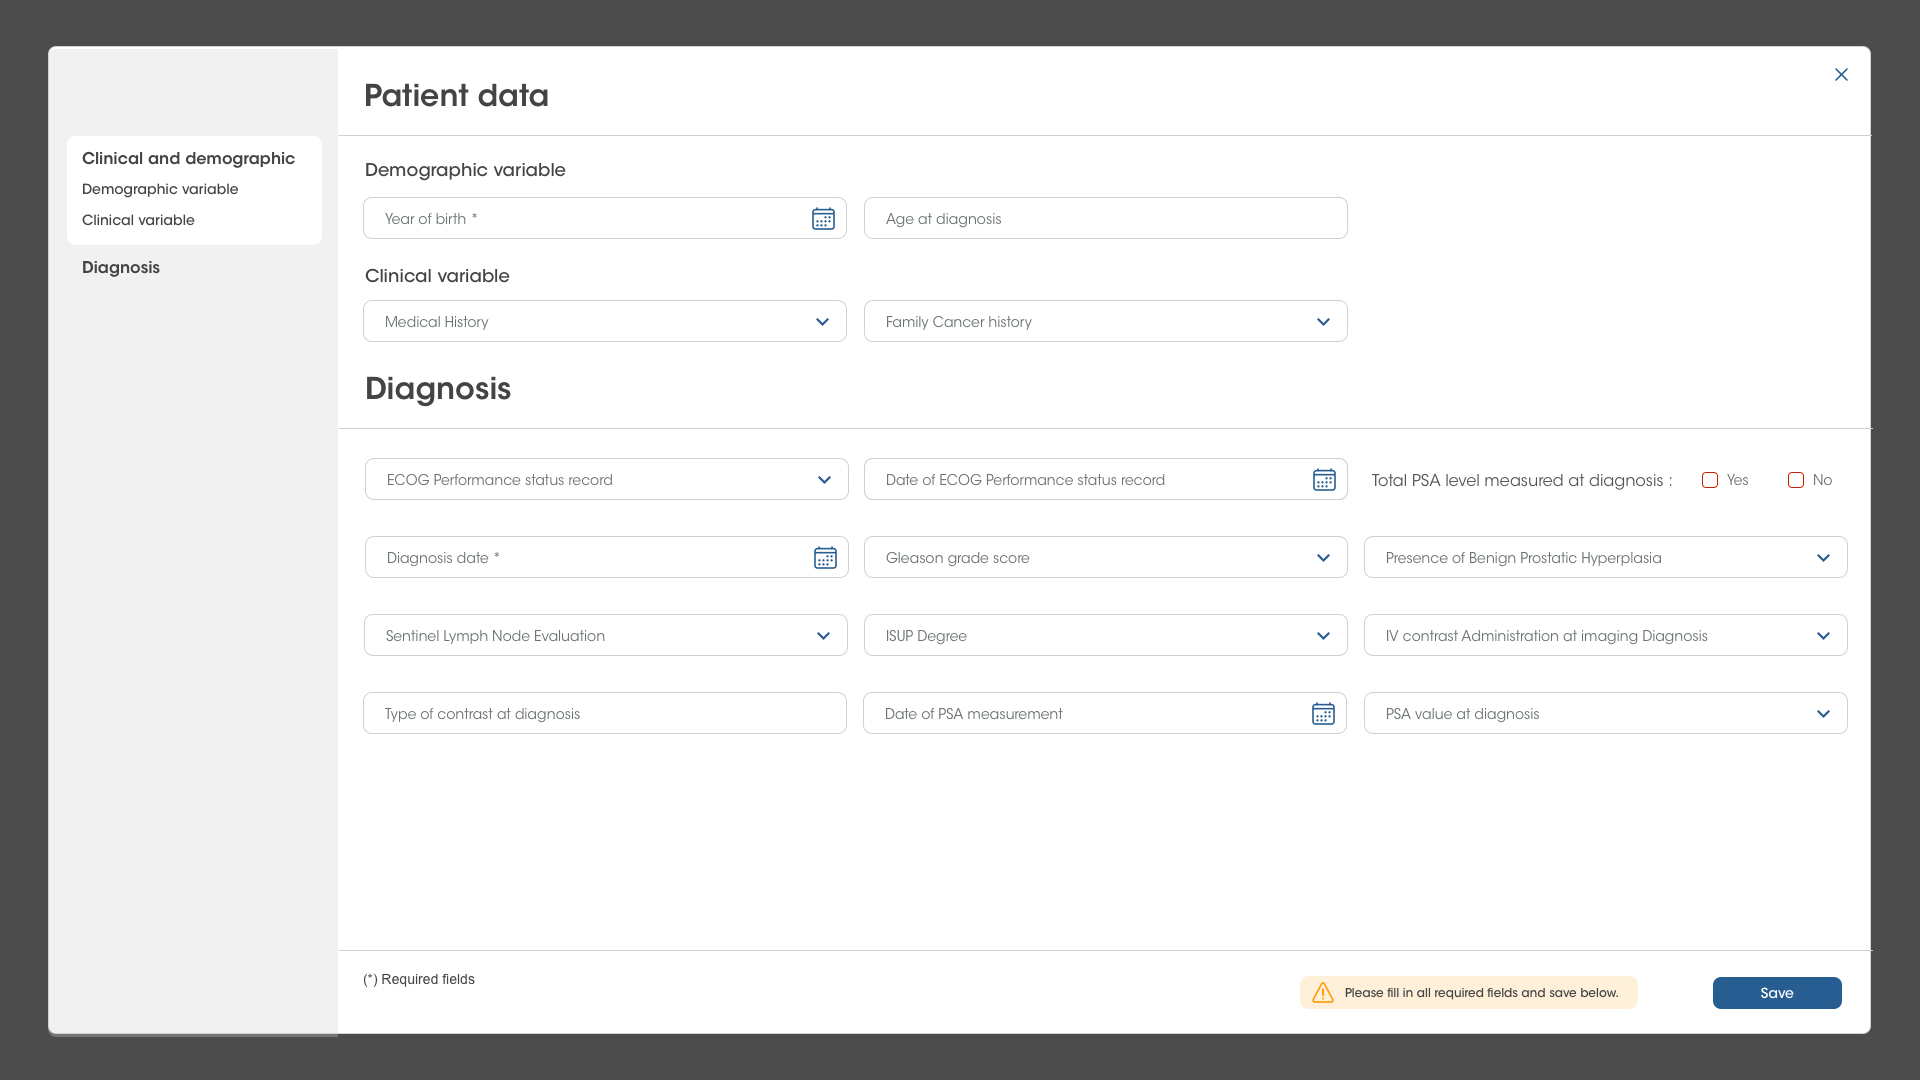

eCRF interoperability

Real-time integration of imaging biomarkers quantification with electronic data capture (EDC) for clinical trials. QP-Insights platform also offers an eCRF customized for each specific clinical study.

Example of an eCRF integrated in QP-Insights for localized prostate cancer